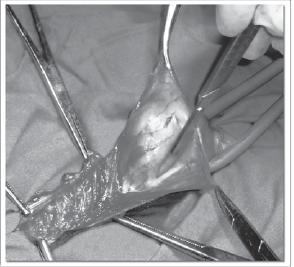

Cirugía de las hernias de la pared abdominal. Libro realizado por el cirujano Jorge F. Abraham donde en el mismo se muestran y describen algunos instrumentos, suturas y materiales protésicos usados en las reparaciones herniarias, elementos de gran importancia sobre todo para cirujanos de reciente promoción. Se explican técnicas quirúrgicas útiles para la reparación de las hernias de la pared y se incluyen algunas originales del autor.

En el libro se muestran y describen algunos instrumentos, suturas y materiales protésicos usados en las reparaciones herniarias, elementos de gran importancia sobre todo para cirujanos de reciente promoción. También se explican técnicas quirúrgicas útiles para la reparación de las hernias de la pared y se incluyen algunas originales del autor.